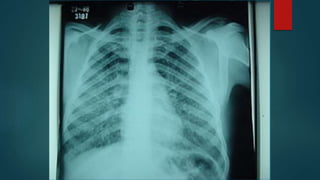

Radiografía

de Tórax

Patrón Alveolar

Patrón Bronconeumónico

Patrón Intersticial